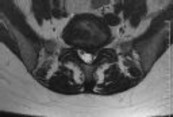

Figures 1 and 2 show sagittal and axial MRI from an 83-year-old woman with an ataxic gait, loss of dexterity, and intermittent loss of bowel and bladder control. The symptoms have been getting progressively worse over the past several weeks.

What disease process is most likely the cause of the patient’s symptoms?

4. Pigmented villonodular synovitis Discussion: B

The patient has a pannus at the C1-2 articulation that is compressing the spinal cord and causing myelopathy symptoms. The development of a pannus at this location has been associated with rheumatoid arthritis. Steinberger and associates showed increased morbidity and mortality when using an anterior approach and the surgery took longer than 4 hours. Chieng and associates showed better outcomes and lower complications rates using a posterior approach.

CLINICAL SITUATION

When discussing anterior versus posterior surgical techniques, you counsel this patient that

Discussion: A